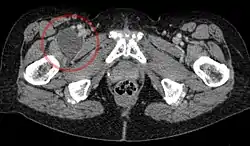

Iliopectineal bursa

Enlarged iliopectineal bursa in CT - scan

The iliopectineal bursa or the iliopsoas bursa is a large synovial bursa that separates the external surface of the hip joint capsule from the normally just the tendon of the iliopsoas muscle.[1]

The most proximal of part the iliopectineal bursa lies on the iliopubic eminence of the superior pubic ramus. The iliopectineal bursa passes across the front of the capsule of the hip joint and extends distally downwards almost as far as to the lesser trochanter.[2]